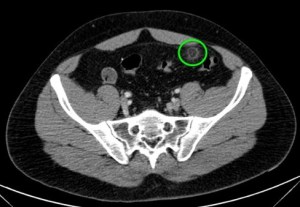

Se sospecha diverticulitis, se realiza TAC de abdomen:

Al igual que el caso anterior, nos encontramos nuevamente ante una apendagitis. Esta vez la sospecha era por diverticulitis, la anterior creíamos enfrentarnos a una apendicitis probablemente.

TAC: Imagen oval con aumento de la atenuación central, inferior a 5 cm de diámetro, contigüa al colon, con afectación de la grasa periférica. El aumento de la atenuación central es un signo de trombosis venosa muy útil para el diagnóstico, pero su ausencia no excluye en diagnóstico de apendagitis. Otros hallazgos, como aumento de la pared colónica o formación de abscesos son raros. Aunque los síntomas remiten en dos semanas, los cambios en la TAC pueden prolongarse más tiempo (pueden mantenerse, disminuir o quedar una atenuación residual), aunque en 6 mese suele haber remitido completamente. En Ecografía suele observarse en el área de máxima sensibilidad al dolor, una masa hiperecogénica, inferior a 5 cm, no compresible, adyacente al colon y sin señal Doppler.